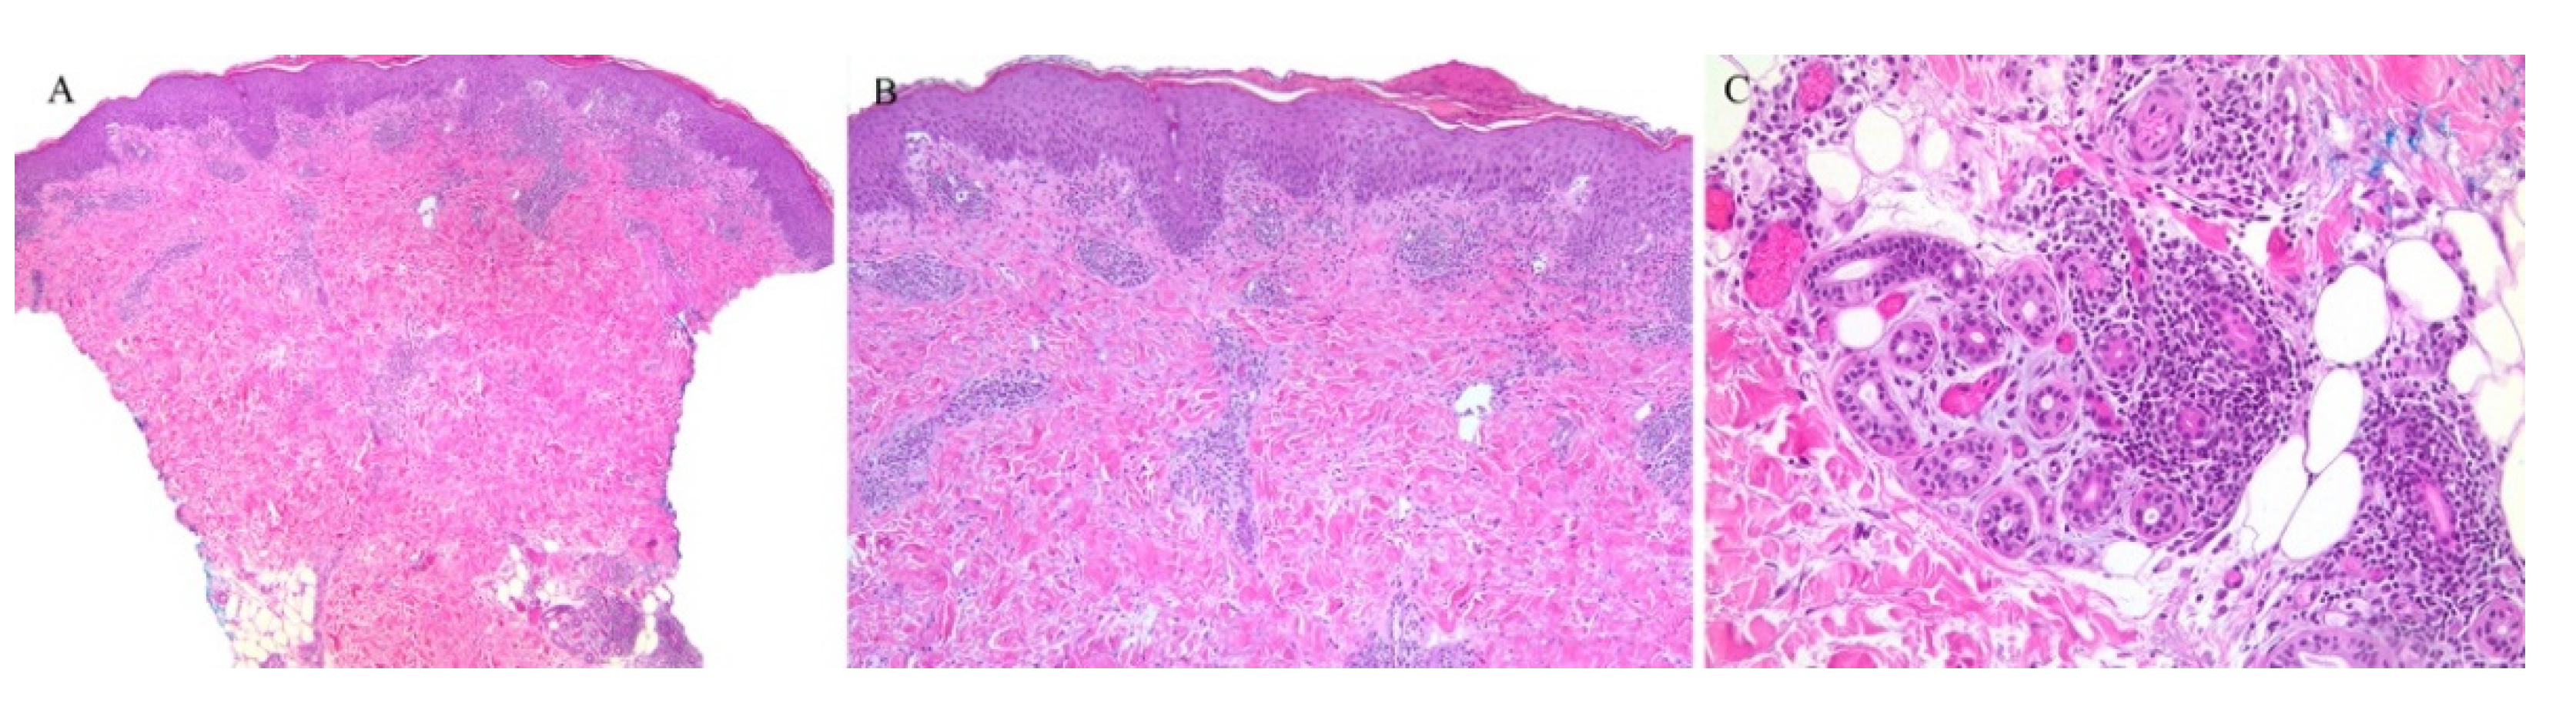

3.2. Lichen Striatus

Lichen striatus (LS) is an uncommon, self-limiting eruption of linear papules that follow the lines of Blaschko. The histopathologic findings are generally non-specific. A lichenoid infiltrate with interface dermatitis can be seen, often with a spongiotic dermatitis as well [1,2]. Adnexal involvement is typical. Perifollicular inflammation has been noted in lichen striatus biopsy specimens [34] (Figure 6). In one study looking at the histologic features of thirty-seven cases of lichen striatus, appendageal involvement, either perifollicular or perieccrine, was observed in 92% of the cases. Many cases often displayed both follicular and sweat gland involvement at the same time. Given the otherwise non-specific findings of lichen striatus, this appendageal involvement prompted the authors to suggest this finding to be part of the diagnostic histopathologic criteria of lichen striatus [35].

The syringotropic feature of LS has also been described in another study. Not only was lymphocytic infiltration of the secretory coil of the eccrine gland noted in all cases studied, but also the presence of eccrine hyperplasia was observed in two cases. Eccrine hyperplasia is a feature of syringotropic mycosis fungoides. Although the clinical presentations of lichen striatus and syringotropic mycosis fungoides are vastly different, their histopathologic features may overlap, and thus awareness of this syringotropic feature of lichen striatus is of utmost importance for dermatopathologists [36].

Figure 6. (AC) Lichen striatus with perifollicular and perieccrine inflammation.